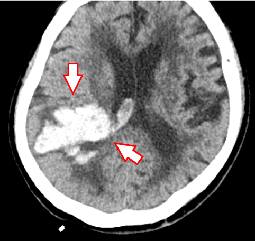

(下図)右片麻痺と意識障害で発症した左内頸動脈閉塞症で、ペナンブラ血栓吸引カテーテルとステント型血栓回収機器で血栓回収療法を施行しました。完全再開通が得られ、症状は改善しました。

急性脳主幹動脈閉塞症

術中の様子

血栓回収の術後

急性期脳主幹動脈閉塞症

脳梗塞の中でも重症な急性期脳主幹動脈閉塞症については、迅速な診断を行い血栓回収療法が開始できる体制が極めて重要です。しかしながら横浜市においても、24時間365日血管内治療に対応できる施設は決して多くないのが現状です。当院は脳血管内治療医の増員によって常時治療可能な体制を整備し、脳神経外科・脳神経内科で共同して診療に当たっています。治療に当たってはステント型血栓回収機器や血栓吸引カテーテルを駆使して、80~90%の症例で有効な再開通を得ています。